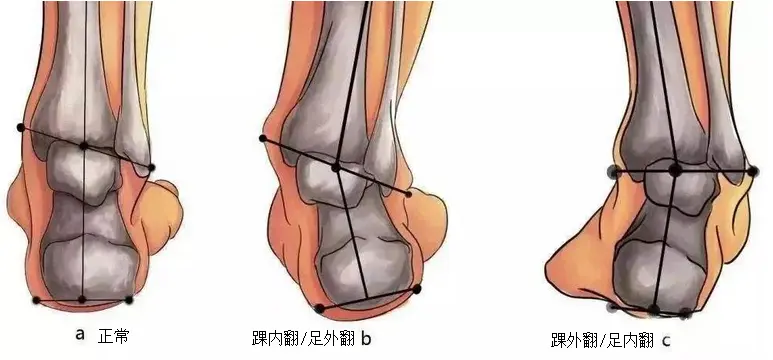

从生物力学来说,下肢力线也是“双腿的重力线”,重力沿着此线向下传递,膝关节的中心出现在这条线上才能维持关节内外侧的压力平衡。动态的平衡也一样,这就需要髋关节和踝关节的控制能力进行参与。力的传递是直的,不会随着骨骼形状做弯曲的传递,正常的下肢力线是髋关节中心与踝关节中心的连线,通过膝关节中心。足部的前侧力线是从胫骨纵轴出发,经过踝关节中心再经过第二跖骨到达第二脚趾。

足的后侧力线是跟骨轴与胫骨干长轴平行。

足的后侧力线是跟骨轴与胫骨干长轴平行。

简单的下肢力线自测方法是站姿取自己腹股沟中心,髌骨中心,踝关节中心三个点的连线看直不直。足的前侧力线是看第二跖骨头和踝关节中心的连线与胫骨是否在一条直线上。足的后侧力线是站姿看跟腱是不是垂直地面。

简单的下肢力线自测方法是站姿取自己腹股沟中心,髌骨中心,踝关节中心三个点的连线看直不直。足的前侧力线是看第二跖骨头和踝关节中心的连线与胫骨是否在一条直线上。足的后侧力线是站姿看跟腱是不是垂直地面。

因为足踝的复杂结构不完全等同于其他关节,它的外展内收被定义为了外翻和内翻,水平旋转则被定义为了外展和内收。

足踝为了适应复杂多变的地形,它的运动方式不同于其他关节那样频繁进行屈、伸、展、收、旋这样单一方向的运动,而是以动作组合的形式出现,分为旋前(足背屈,外翻,外展)和旋后(足跖屈,内翻,内收)。

足踝为了适应复杂多变的地形,它的运动方式不同于其他关节那样频繁进行屈、伸、展、收、旋这样单一方向的运动,而是以动作组合的形式出现,分为旋前(足背屈,外翻,外展)和旋后(足跖屈,内翻,内收)。

过度的足旋前可以是外八字脚,足踝通过踝关节和距跟关节使整个足相对小腿做了一个包含了外旋的动作,所以足旋前时小腿相对的做了一个内旋,足旋后反之就是小腿相对足踝做了外旋。

为什么说足旋前“可以是”外八字脚,是因为髋关节的旋转可以引起整个下肢的旋转,如果髋关节过度外旋,脚尖朝向也是会跟着转的,但足踝相对小腿的位置没变。

并非到此为止了,因为足在步态中的功能,所以过度的足旋前会连带足弓塌陷出现扁平足,降低旋前侧的所有体表解剖标志物(如股骨外侧髁,大转子,髂前上棘等等)的高度出现长短腿,小腿的相对内旋也可以带动髋关节内旋出现膝内扣,然后引起髌股关节或者髂胫束的问题等等…

过度足旋后的逻辑相反。

了解足的旋前和旋后就可以理解,外八内八的脚并不是一个纯粹的水平面上的旋转,所以不要企图依靠改变锁片角度去矫正脚的位置。 调整锁片角度只是水平面上的旋转,跟足旋前旋后的机制不同,强行制造脚的水平旋转不会出现足踝的动作,而是引起整个下肢出现旋转,最后改变下肢朝向之后,引起下肢力线歪斜。

足踝的内翻肌有胫骨前肌和胫骨后肌(上图可见)。

足踝的内翻肌有胫骨前肌和胫骨后肌(上图可见)。

外翻肌有腓骨长肌,腓骨短肌,第三腓骨肌。